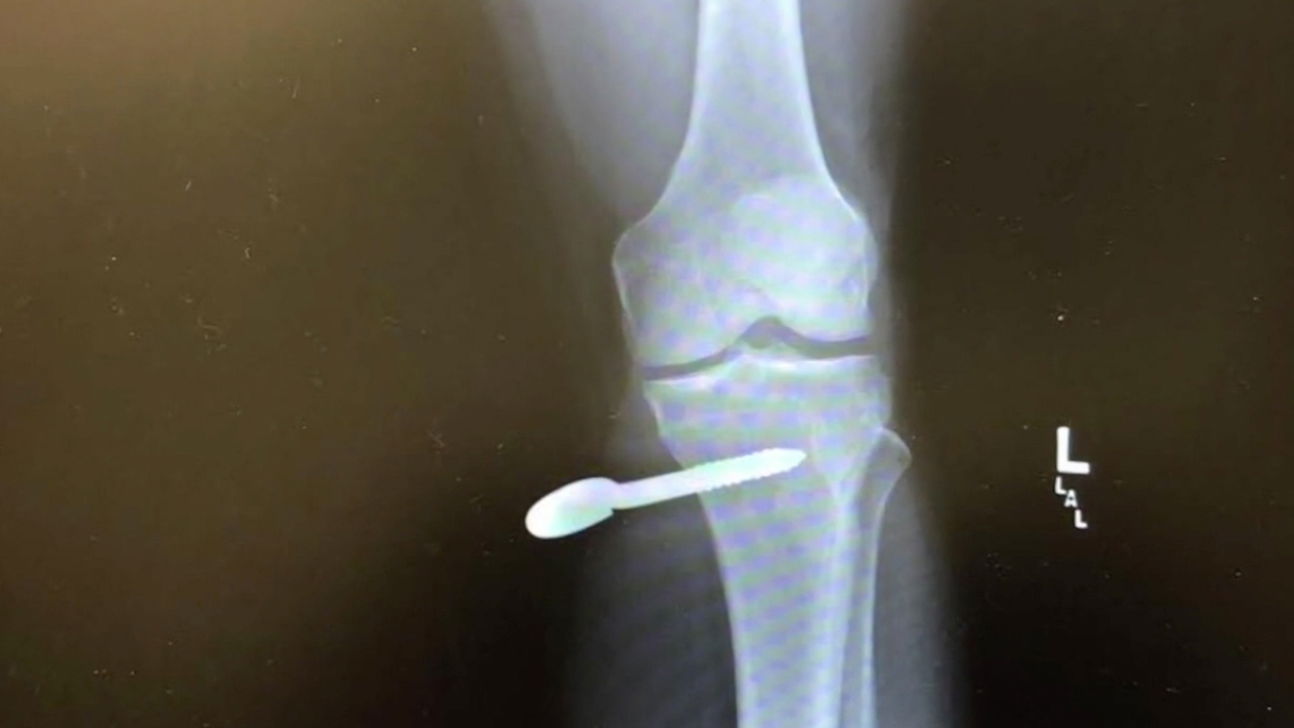

The force of his swing ripped one of the bolts out of the ground and sent it spiraling into Gutierrez’s leg, piercing his bone.

Gutierrez was rushed to a hospital where doctors unscrewed the hardware.